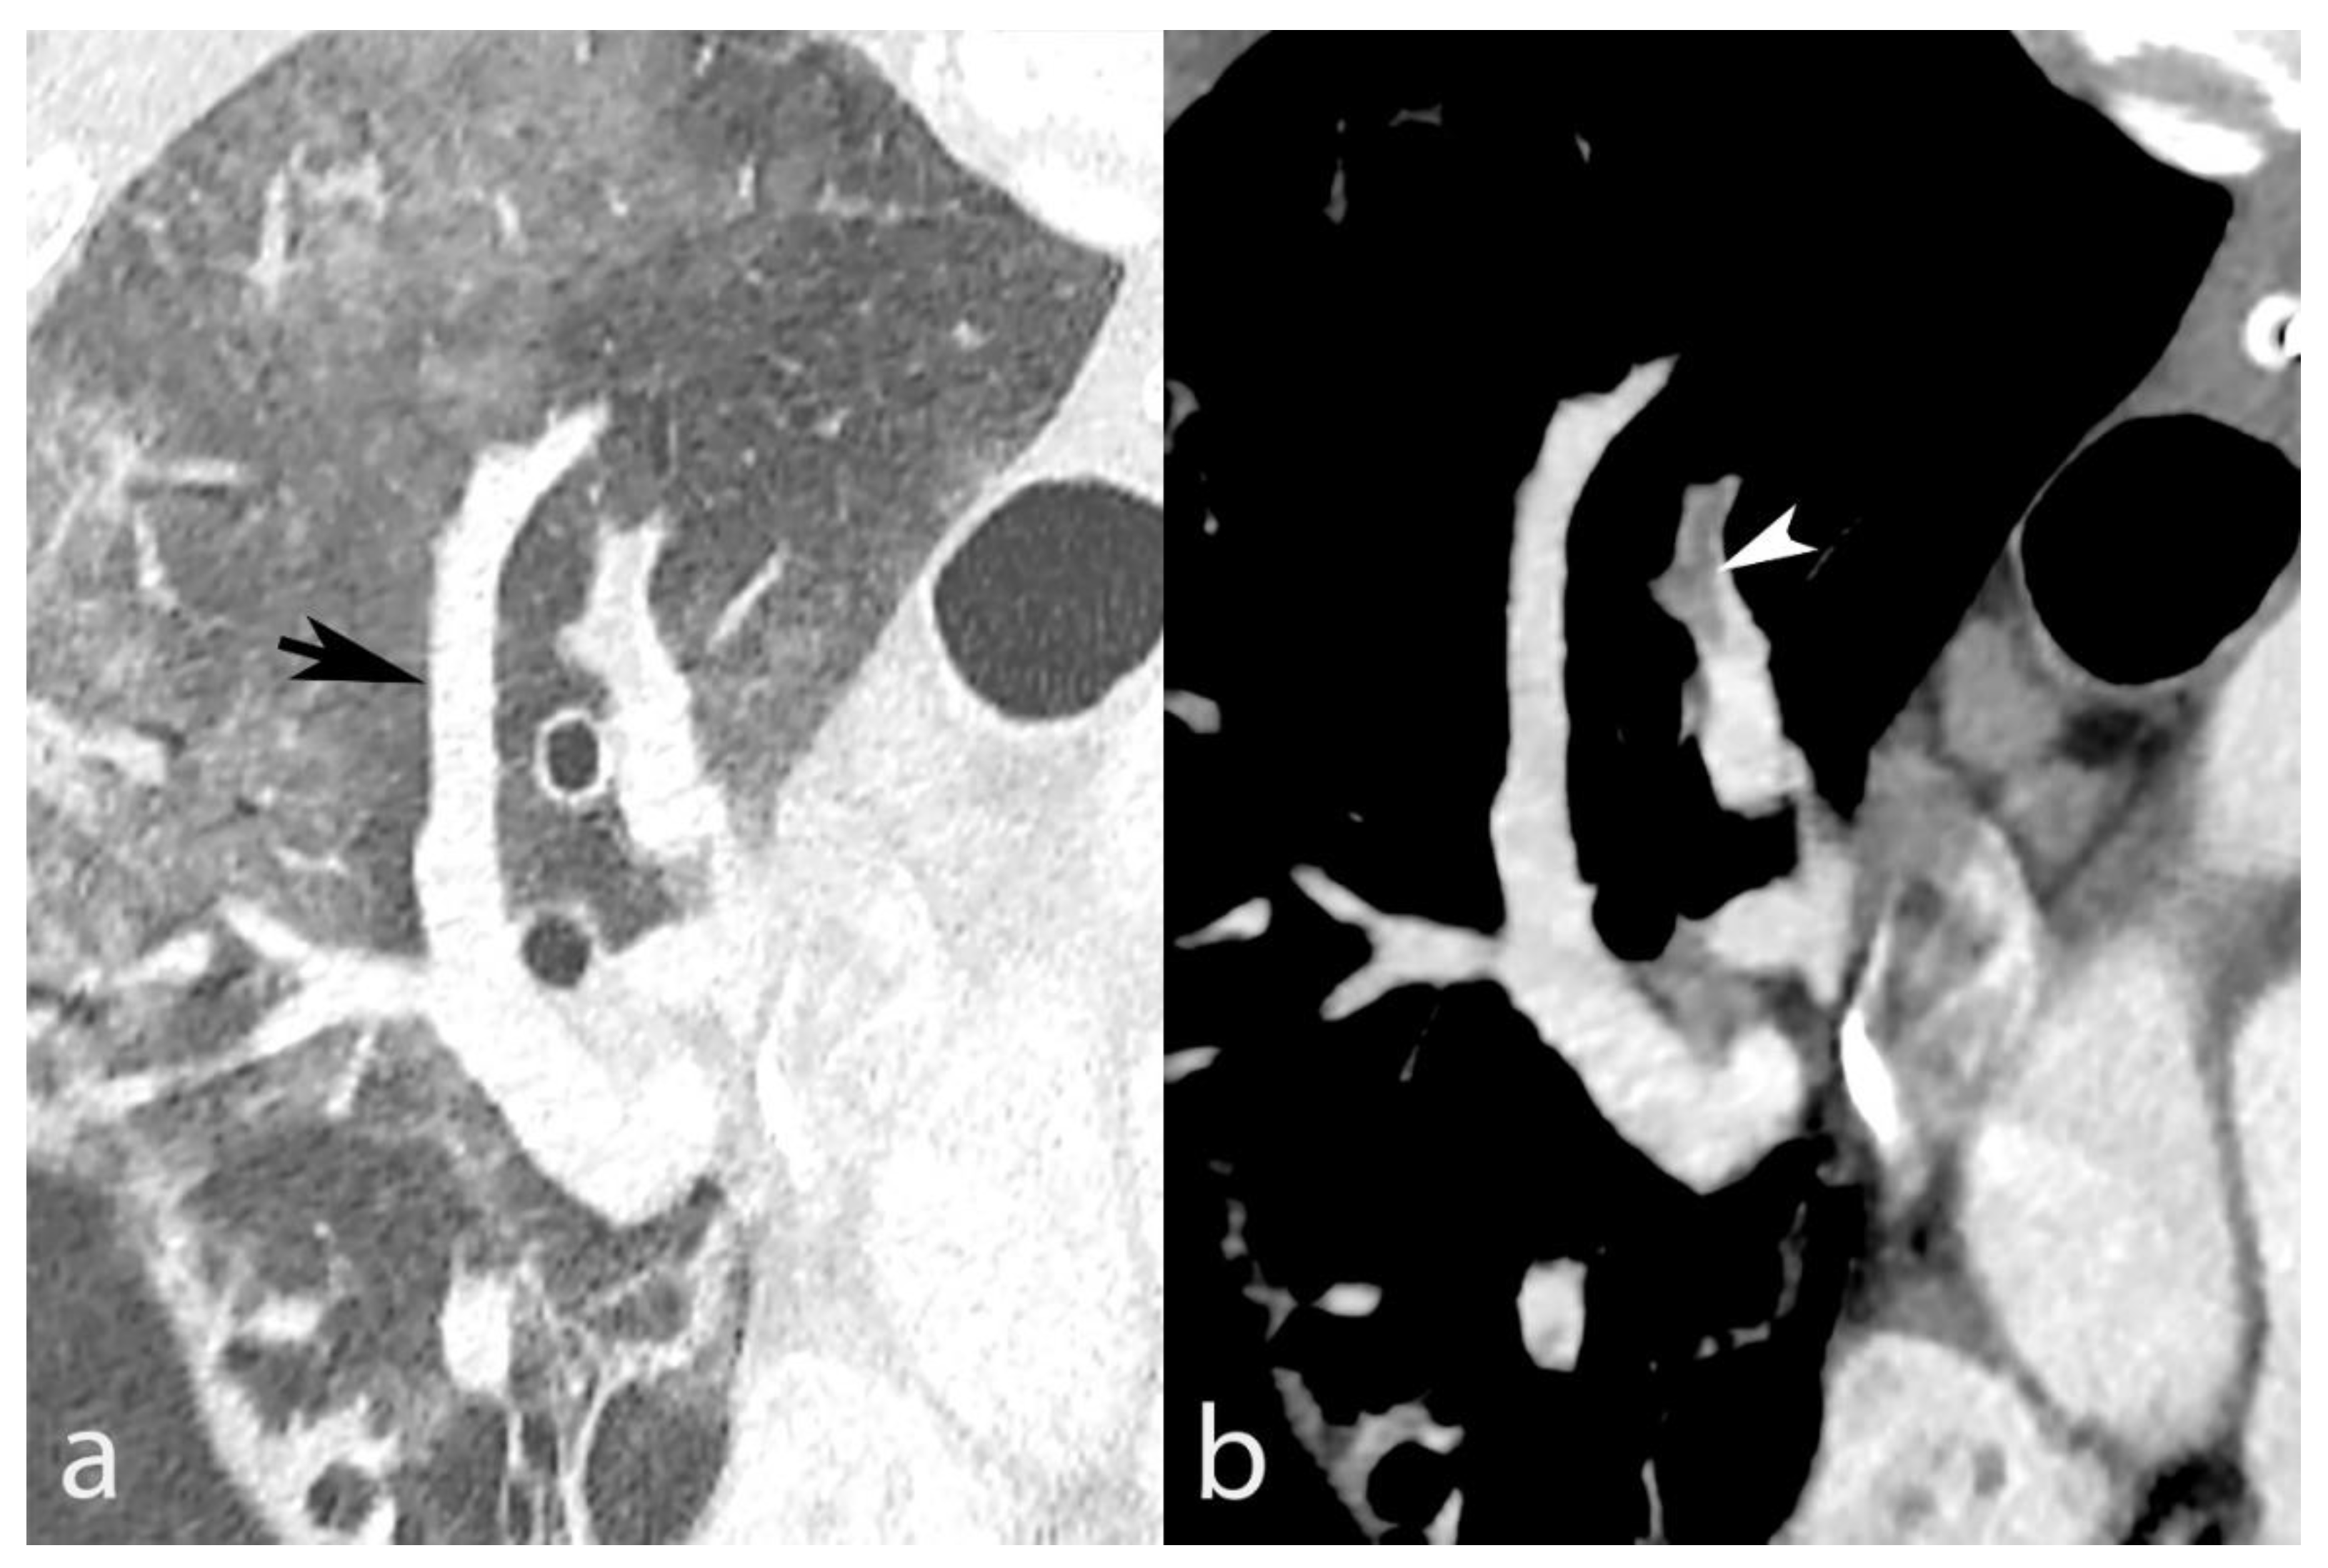

Figure 6.

COVID-19 pneumonia with AO and VC (panel (a), black arrow) in a 63-year-old man. Acute PE (panel (b), white arrowhead) was found in the right upper lobe. The concomitant presence of PE and VC raises the question of arteriovenous anastomosis dysregulation increasing blood flow in the vein despite the arterial obstruction.

In addition, Table 3 demonstrates that among the 75 emboli located in segments without VC, 46 were located within 200 (23%) segments without AO vs. 29 emboli within 124 (23.4%) segments with AO (p = 0.936), indicating that pneumonia-related hyperemia alone did not influence PE location significantly and is not the only driving mechanism. Furthermore, AO severity did not significantly influence the PE rate overall: 139 emboli were found within 513 (27.1%) segments with <50% AO vs. 139 emboli within 473 (29.4%) segments with >50% AO (p = 0.424). This finding suggests that VC drives the significant dependency of PE on AO since AO tended to affect the PE rate in segments with VC, although without reaching statistical significance (15% PE without AO vs. 28.9% with AO; p = 0.071), likely due to a lack of statistical power. The potential relationship between VC and PE in the same segment is supported by cases in which VC and PE coexist in a segment without AO (Figure 7).

Figure 7.

Mild AO in the right middle lobe (panel (a), black arrowhead), without associated VC in an 85-year-old man. On the other hand, distinct VC is seen in the right lower lobe (panel a, black arrow) with concomitant PE (panel (b), white arrowhead), supporting the potential role of VC in PE’s distribution.